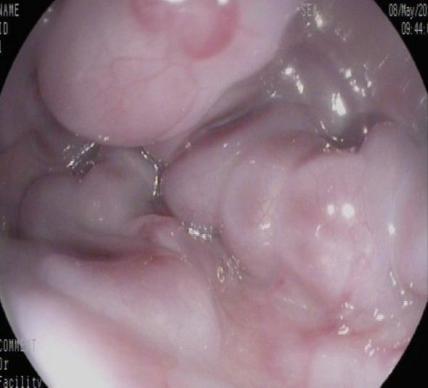

• 内镜序贯治疗儿童门静脉高压症伴食管胃静脉曲张破裂出血的疗效观察

2026, 32(3):51-57. DOI: 10.12235/E20250458

摘要 (30) HTML (26) PDF 2.07 M (31) 评论 (0) 收藏

摘要:目的 评估内镜序贯治疗儿童门静脉高压症(PHT)伴食管胃静脉曲张破裂出血(EVB)的临床疗效。方法 回顾性分析2010年6月-2023年2月于该院内镜下序贯治疗的PHT伴EVB的患儿21例。收集患儿病史特点、内镜表现、疗效和术后生长发育情况,分析所需内镜次数、术后即刻止血率、术后再出血率、术后并发症、生存率和术后长期生长发育情况。结果 患儿平均年龄(6.86±2.95)岁。末次治疗前血红蛋白水平明显高于首次入院,差异有统计学意义(P < 0.01)。共行81次(105项次)内镜下治疗,21例患者接受治疗次数的中位数为4.00(1.00,10.00)次。其中,18例患者接受内镜下套扎治疗,每例次套扎环数为7.0(6.00,12.00)环。内镜下硬化剂注射(EIS)治疗18例,每例次硬化剂用量为(12.29±5.67)mL。内镜下组织黏合剂注射治疗19例,每例次组织胶用量为(2.96±1.24)mL。内镜下即刻止血率为100.00%。6个月内再出血率为4.76%(1/21),6个月以上再出血率为14.28%(3/21)。至随访结束,4例患儿成年,体重指数(BMI)均在正常范围之内;其余17例未成年患儿年龄别体重Z评分(WAZ评分)明显改善(P < 0.01)。结论 内镜序贯治疗儿童PHT伴EVB安全、有效,促进患儿生长发育的同时,可作为外科手术后的补救措施,还可为未手术者提供手术或肝移植的机会。